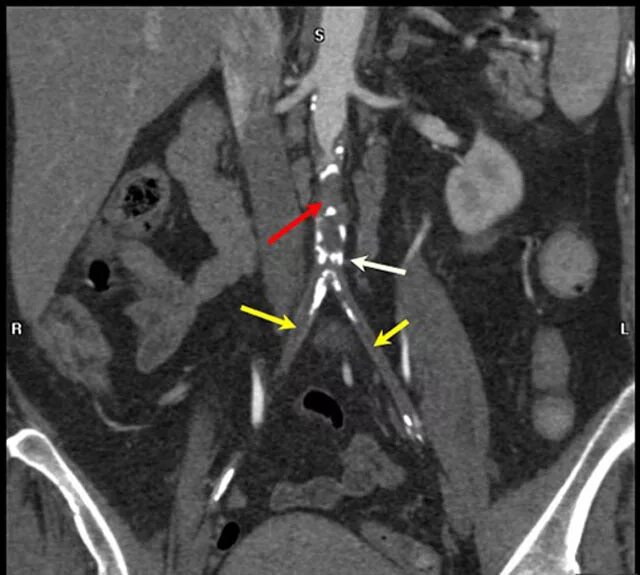

Тромбоз аневризмы аорты